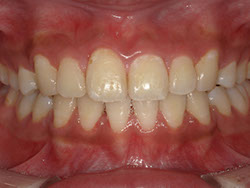

1期治療でスケルトンタイプの拡大装置で歯列拡大後、上下第一小臼歯を抜歯して口元もキレイになりました。

矯正前

矯正中

矯正終了後

始めは虫歯の治療も大暴れでした。

今では笑顔で通院してくれています。